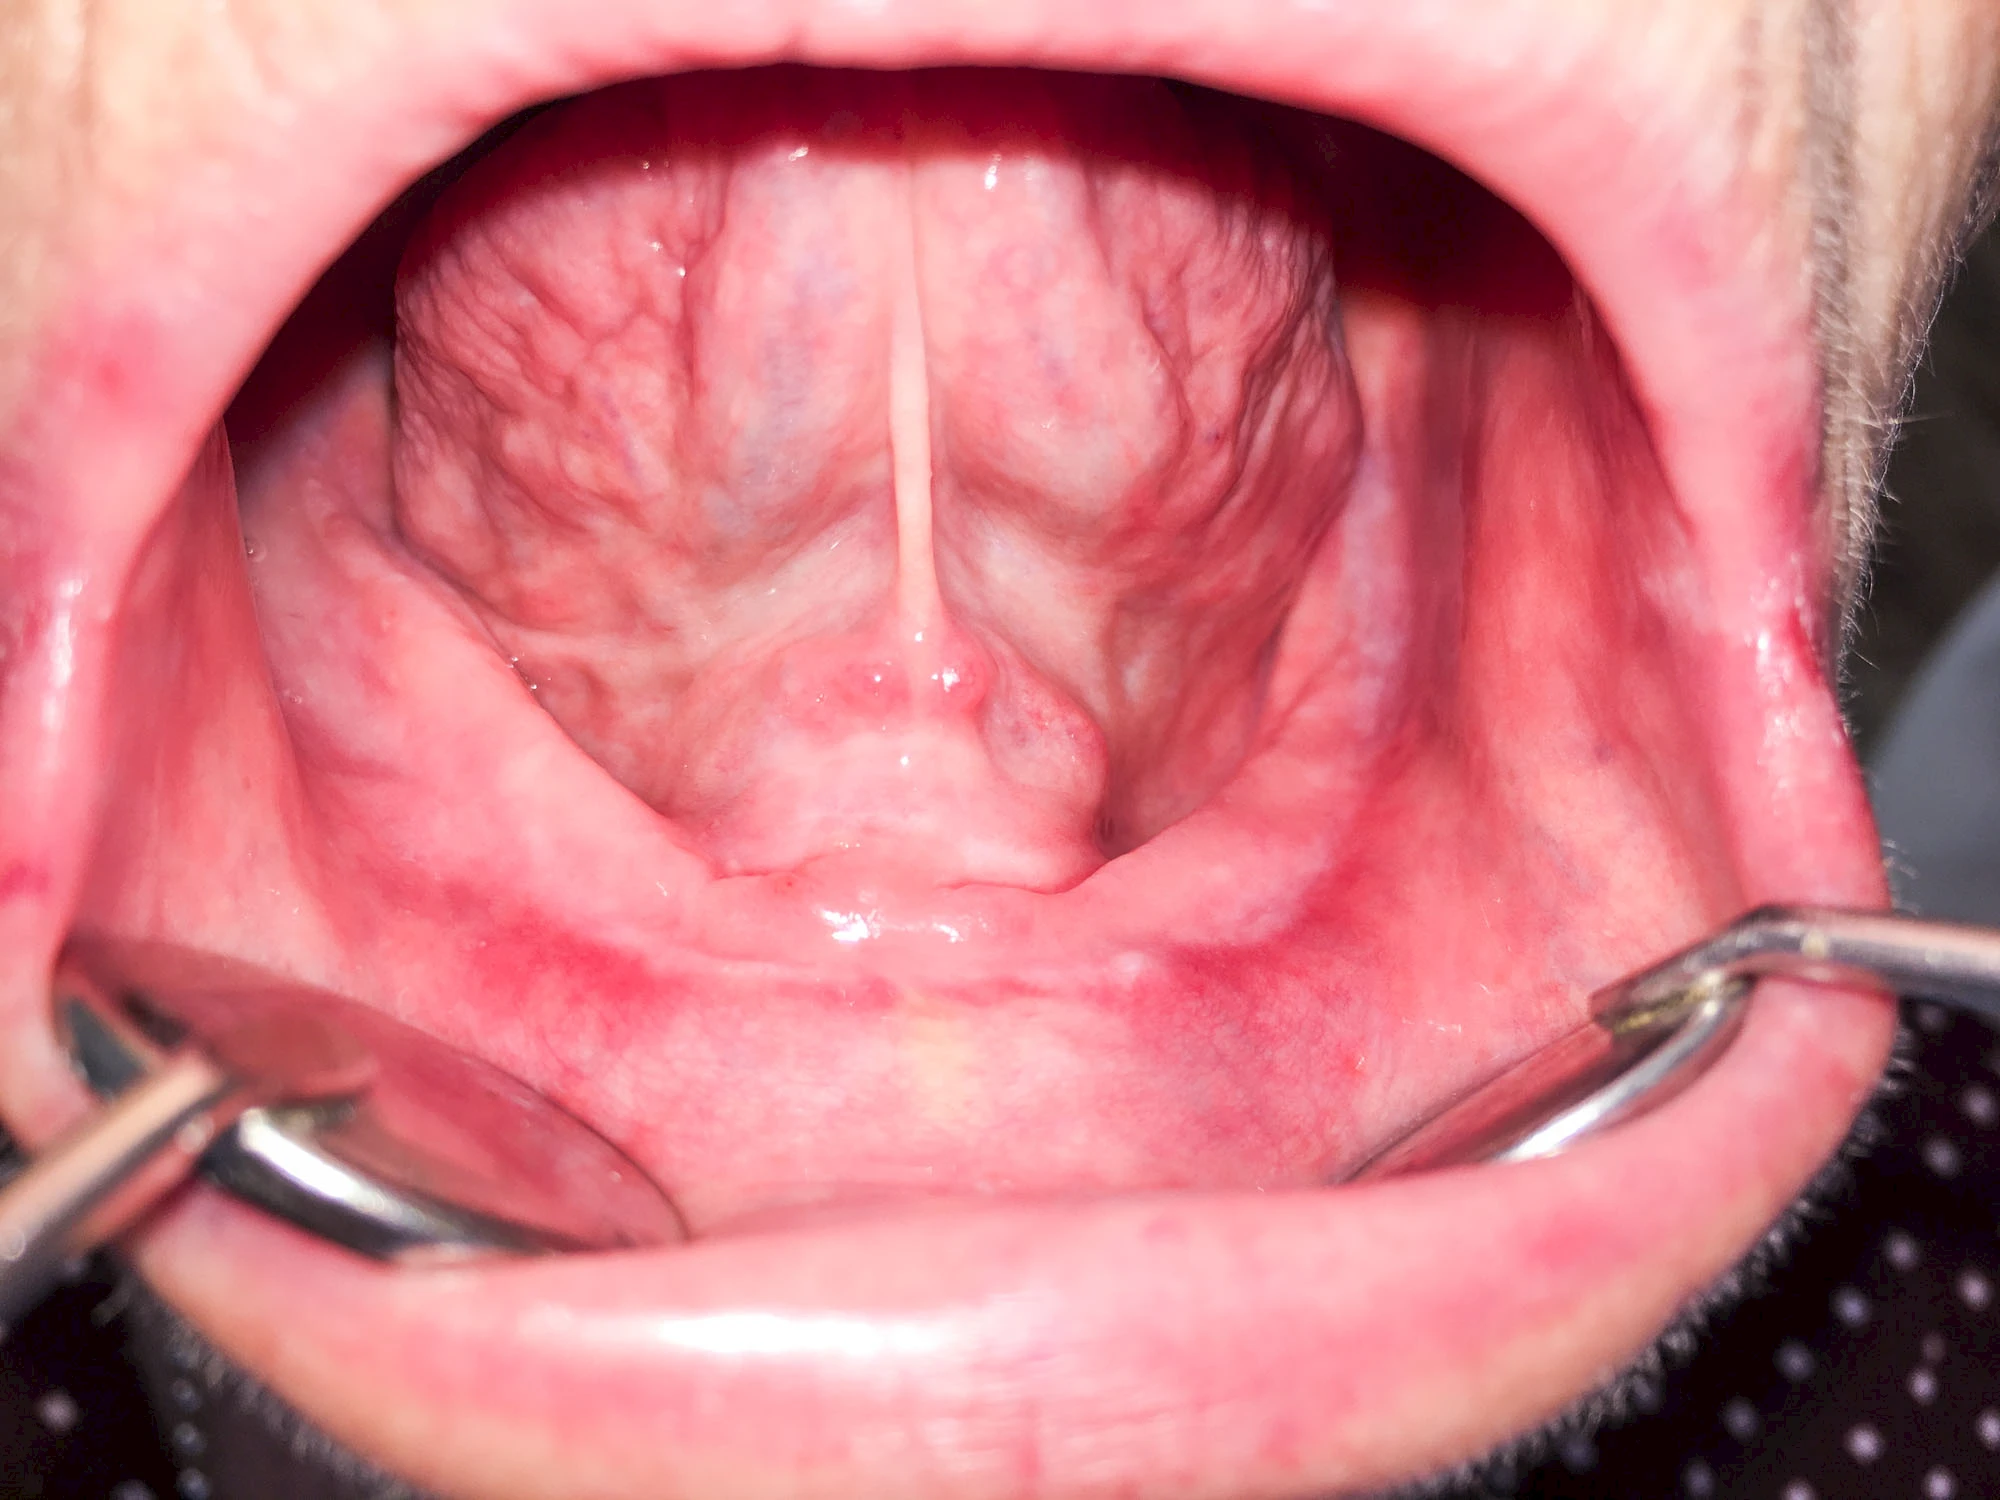

In seltenen Fällen schwindet nur der Knochen, aber nicht die bedeckenden Schleimhäute. In diesen Fällen spricht man von einem sogenannten "Schlotterkamm".